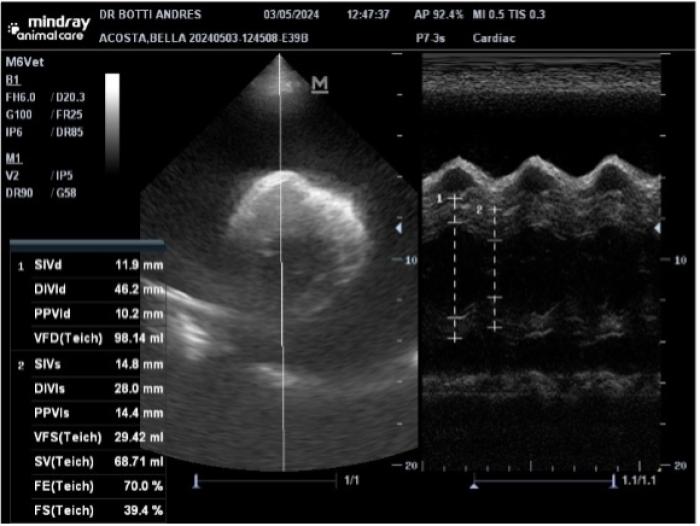

Una emergencia por un derrame es indudablemente más frecuente cuando afecta al saco pericárdico. Los tumores cardíacos más frecuentes son los hemangiosarcomas (HSC) cardíacos y las neoplasias neuroendocrinas del cuerpo aórtico (NCA). En el caso del HSC los derrames suelen ser hemorrágicos y en los NCA serosanguinolentos. El espacio pericárdico es el que menos cantidad de líquido puede alojar, por lo cual las colectas pueden llevar a un aumento de presión dentro del saco que puede colapsar el corazón derecho llevando a una emergencia. El paciente puede tener al examen general sonidos cardíacos apagados, pulso débil, signo hepatoyugular, debilidad, congestión hepática y llevarlo directamente a un estado de shock. Los hallazgos en las radiografías simples pueden hacer sospechar de una colecta pericárdica debido al hallazgo típico de una silueta cardíaca de aspecto globoso y la ultrasonografía confirma la sospecha (Figura 3).

Con la ultrasonografía se puede evidenciar la colecta pericárdica con facilidad e incluso puede ser usada para guiar el drenaje. El líquido pericárdico obtenido debe acondicionarse con y sin anticoagulante, centrifugar y analizar el sedimento para realizar citología. Es importante recordar que, si bien está indicado el análisis del líquido, lamentablemente pocas veces alcanza un nivel de confianza tal que permita validar un diagnóstico definitivo; la concentración mediante cytospin o citocentrífuga permite aumentar la sensibilidad de la muestra.